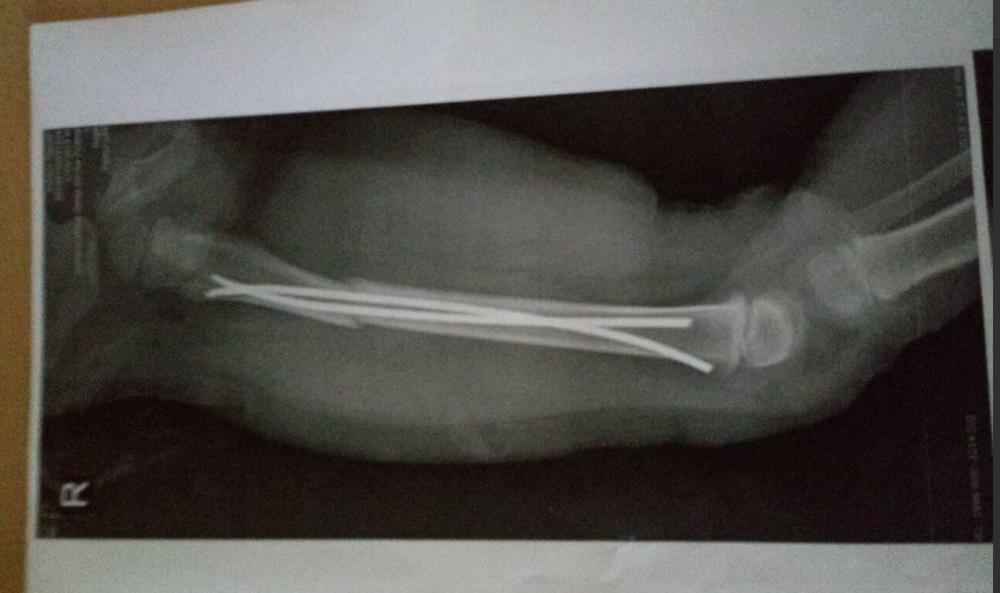

Malom Ognjenu iz Sremske Mitrovice (3) je potrebna novčana pomoć za troškove operacije i dalje lečenje zbog preloma butne kosti, zbog čega su mu postavljene i dve šine.